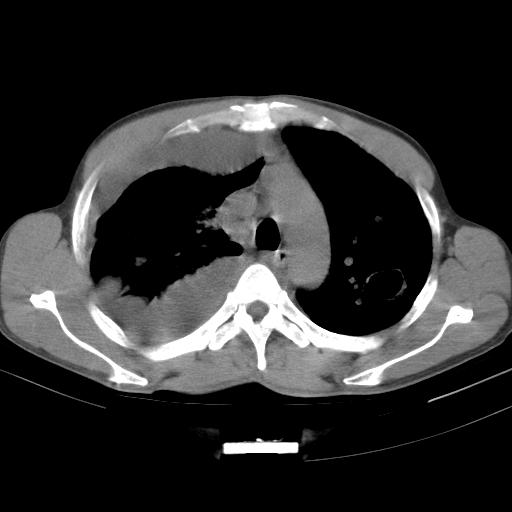

男性,44岁,结核病史多年。现胸闷气短,咳嗽,偶咳血。

右侧胸腔积液

右肺下叶不张

双肺多发结节影最分空洞形成考虑占位不除外结核

双肺陈旧性病变

1、右侧大量胸腔积液伴右肺压缩性膨胀不全,建议抽液治疗后复查 2、两肺继发性tb伴空洞形成。

1)两肺继发性肺结核伴空洞形成,左肺多发性结核球。2)右侧大量胸腔积液伴右肺部分膨胀不全。3)纵隔淋巴结肿大。